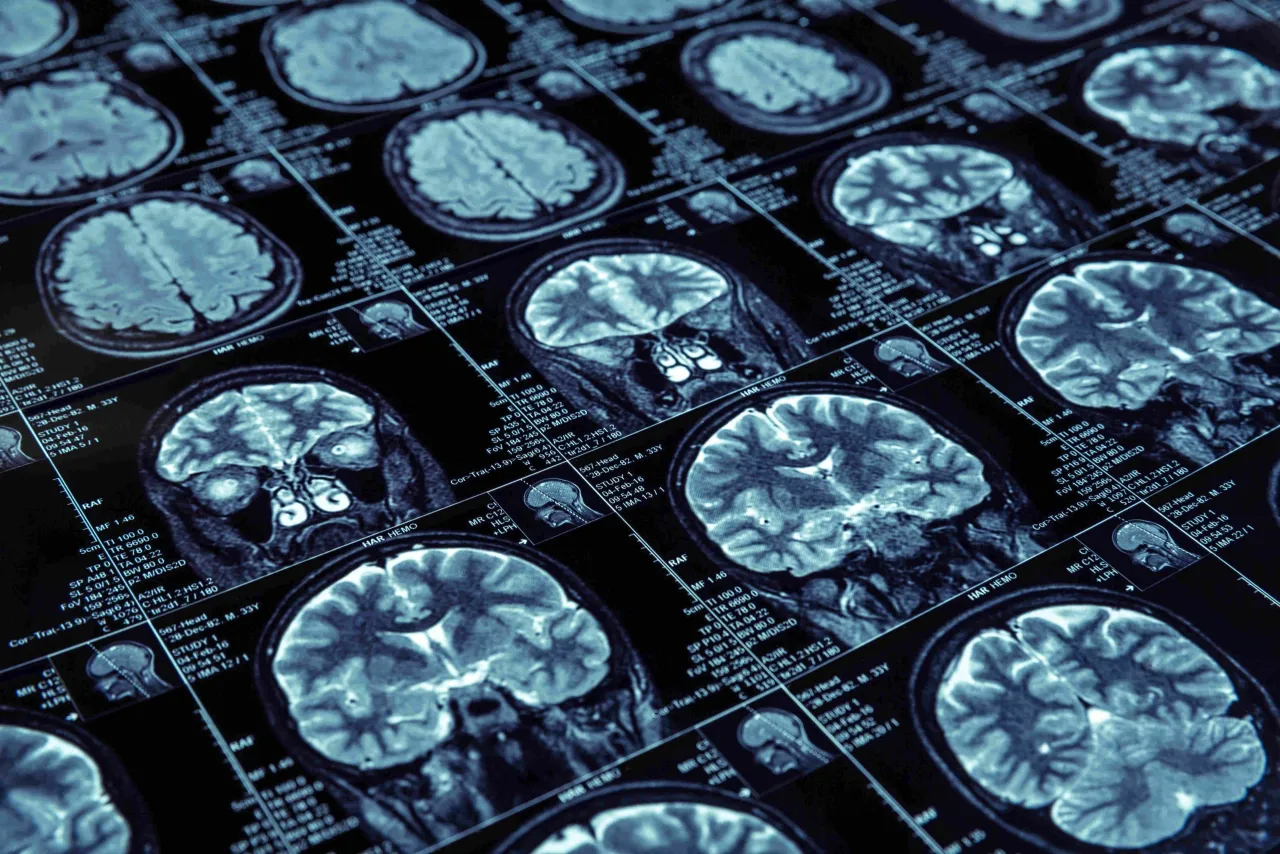

Tomografia komputerowa (TK) głowy to zaawansowana metoda diagnostyki obrazowej, która wykorzystuje promieniowanie rentgenowskie do tworzenia szczegółowych, przekrojowych obrazów struktur wewnątrzczaszkowych. W mojej ocenie, jest to nieocenione narzędzie, szczególnie w diagnostyce neurologicznej i urazowej, ponieważ pozwala na szybkie i precyzyjne "zajrzenie" do wnętrza głowy. Tomograf, obracając się wokół pacjenta, wykonuje serię zdjęć rentgenowskich pod różnymi kątami, które następnie komputer przetwarza w trójwymiarowy obraz mózgu, kości czaszki, zatok i naczyń krwionośnych.

Często pacjenci pytają mnie o różnice między tomografią komputerową a rezonansem magnetycznym (MRI) głowy. Obie metody są niezwykle cenne, ale mają swoje specyficzne zastosowania. Tomografia komputerowa jest zazwyczaj badaniem szybszym i tańszym. Ma również przewagę w obrazowaniu kości oraz świeżej krwi, co czyni ją niezastąpioną w przypadku urazów i udarów krwotocznych. Z kolei rezonans magnetyczny, choć dłuższy i droższy, oferuje znacznie większą precyzję w ocenie tkanek miękkich. Jest to badanie z wyboru przy podejrzeniu guzów, stwardnienia rozsianego czy subtelnych zmian niedokrwiennych. Decyzja o wyborze badania zawsze należy do lekarza, który najlepiej oceni, która metoda będzie najbardziej odpowiednia dla danego przypadku.

Chociaż tomografia komputerowa nie jest głównym narzędziem diagnostycznym w chorobach neurodegeneracyjnych, może ujawnić pewne zmiany zwyrodnieniowe i zanikowe mózgu. Na obrazie z TK można zaobserwować zaniki korowe mózgu, które są charakterystyczne m.in. dla choroby Alzheimera. Pozwala to na ogólną ocenę objętości mózgu i poszerzenia przestrzeni płynowych, jednak dla szczegółowej diagnozy i oceny postępu tych chorób, zazwyczaj preferowany jest rezonans magnetyczny.